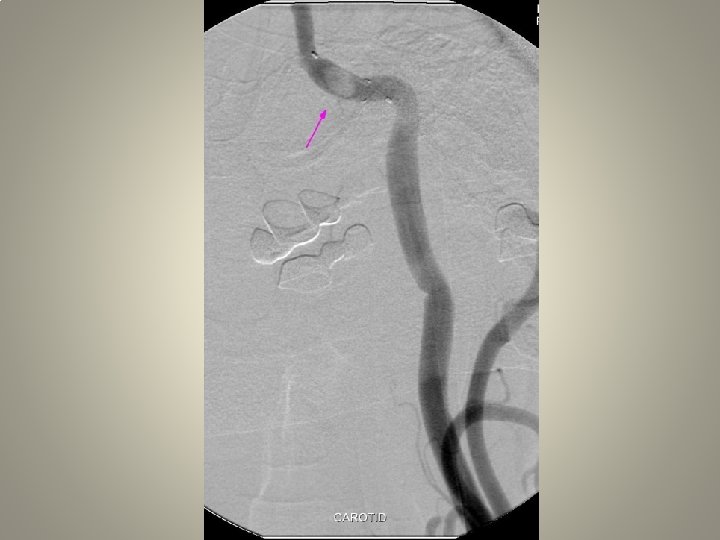

Neden stent? TANDEM lezyon

Neden stent? Distal emboli koruma

Neden stent? Eş zmanlı komplikasyon idaresi